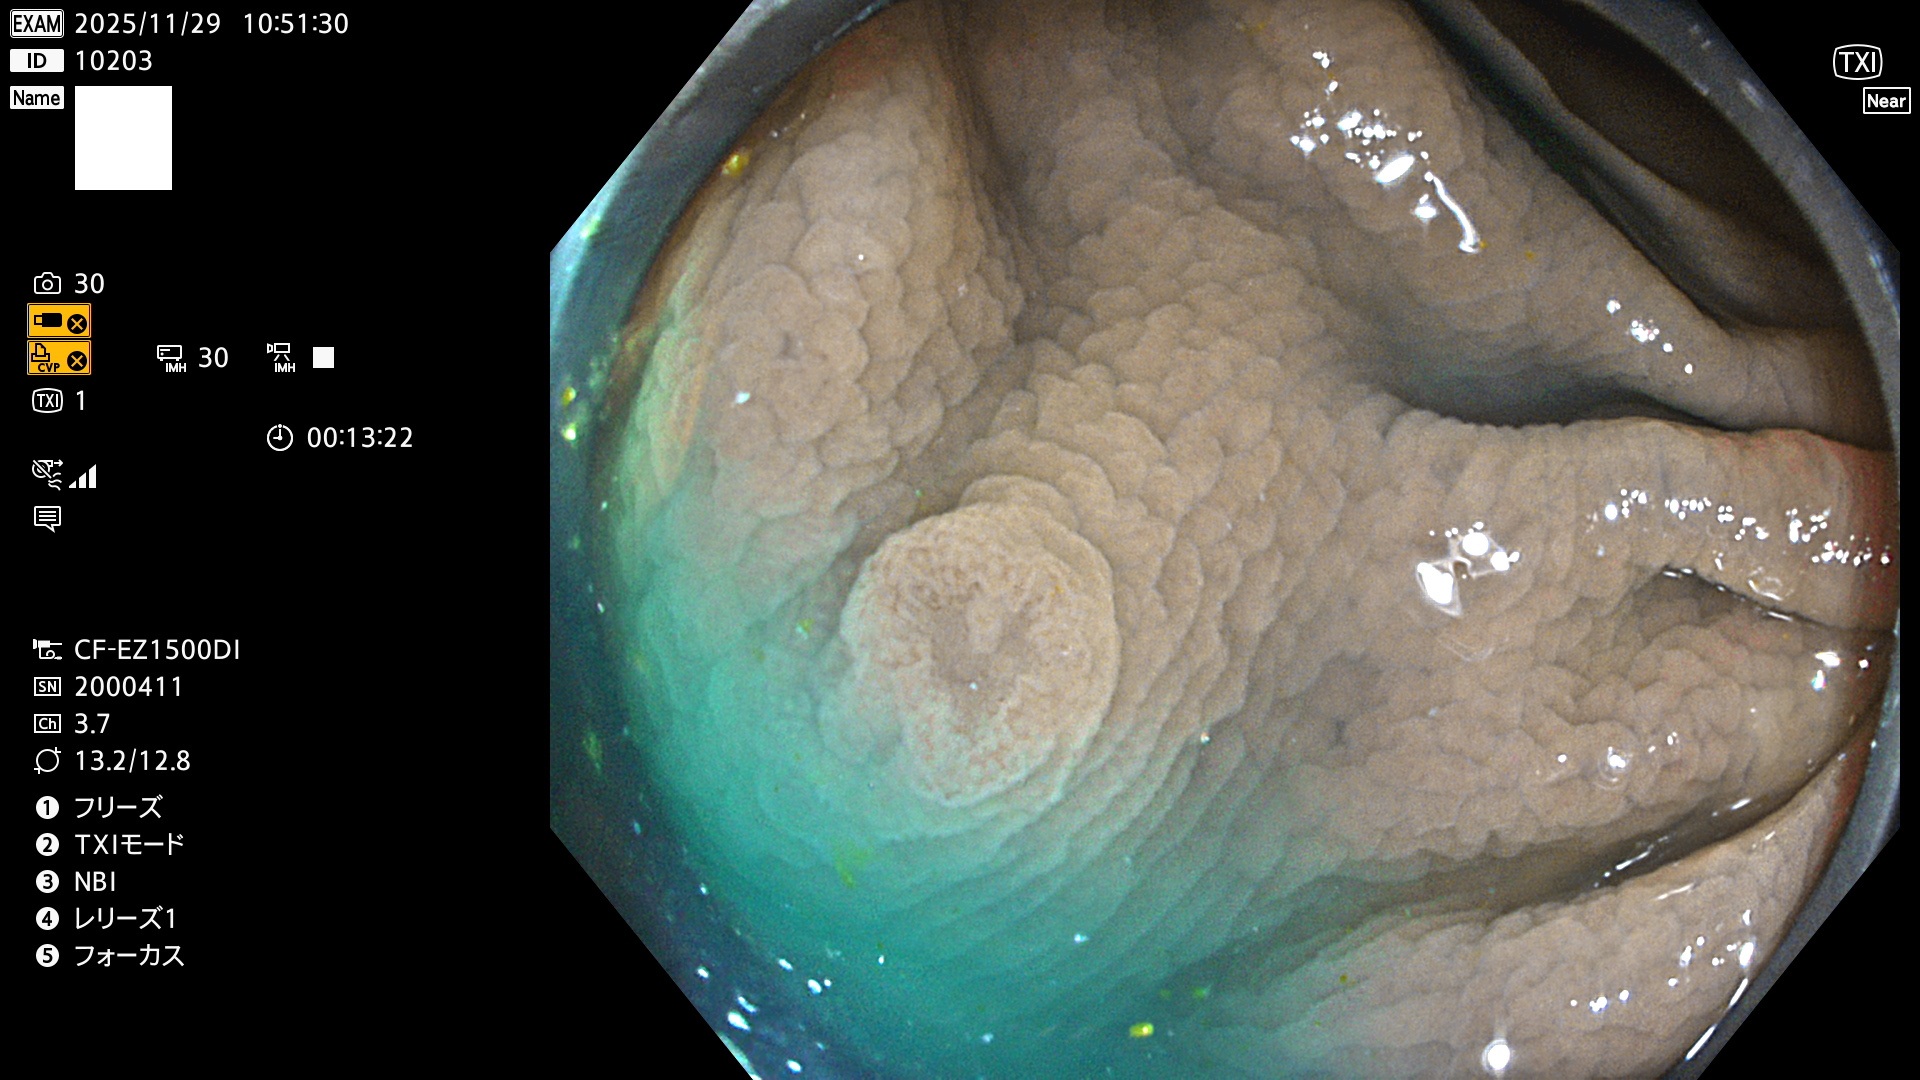

完全に平坦な物をUb、陥凹している物をUcと呼びます。Ubは認識が困難で、Ucはびらん(炎症)と紛らわしいために見落とされやすく、「内視鏡後・大腸癌」の原因になります。

専門的)何故、陥凹していると危険? 癌遺伝子の変異が蓄積すると細胞分裂が盛んになり隆起するのでは?と通常は思われるでしょう。しかし実際は逆です。これは2022年の記事にある「細胞はストレスに直面したら細胞分裂を止める(Dormancy 細胞老化に入り休眠する)という生命の基本的現象」によるものです(Oncogene Stress)。細胞老化を起こすのが癌抑制遺伝子で、この安全装置(ブレーキ)が壊れると癌になります(休眠からの覚醒)。ですから陥凹は「まだ癌では無いが癌化の直前」を意味します。特に「小サイズなのに陥凹している」病変は短期間に腫瘍進化(IntraTumor Heterogenity⇒2021年記事)が起きたことを意味します(=ゲノム不安定性)。

毎週の検査(木・金・土・日)に発見されたUbとUc型・腺腫を、その週の日曜の夜にUPし1週間、提示します。

2025年11月27日〜12月7日の7日間(70件)6個 (Uc_ADR=6個/70人=9%)